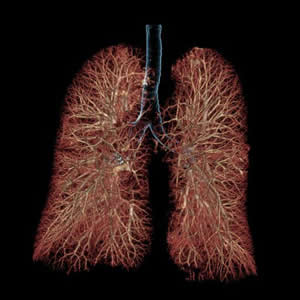

検査は、ベッドに寝ているだけで終了します。また、当院検査は、一回の撮影で同時に複数の輪切り像が得られる最新型ボリュームCTスキャナです。 得られた輪切り画像から下のような精密な立体像を作ることも可能です。

胸部3次元画像